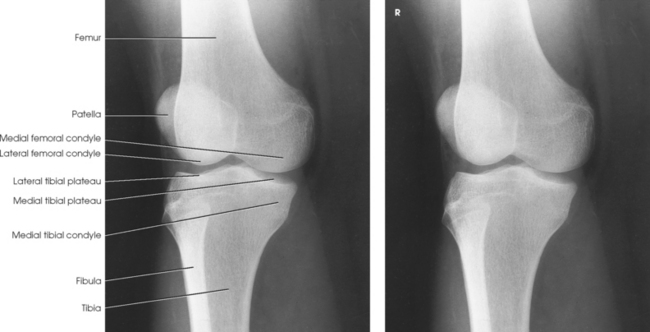

Structures shown: The resulting image shows an AP projection of the knee structures (Fig. 6-121).

Structures shown: The resulting image shows an AP oblique projection of the laterally rotated femoral condyles, patella, tibial condyles, and head of the fibula (Fig. 6-132).

Structures shown: The resulting image shows an AP oblique projection of the medially rotated femoral condyles, patella, tibial condyles, proximal tibiofibular joint, and head of the fibula (Fig. 6-134).